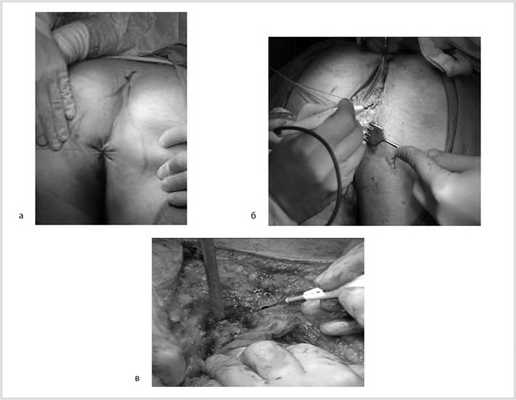

04.04.18 пациенту выполнена симультанная операция: лапаротомия, удаление гигантской неорганной забрюшинной опухоли, резекция опухоли правой почки, закрытие дефекта правой паховой области сетчатым трансплантатом, пластика пупочного кольца местными тканями, дренирование брюшной полости.

После тотальной срединной лапаротомии в забрюшинном пространстве слева обнаружена опухоль размером 20×30 см, неотделимая от левой паранефральной клетчатки, располагающаяся от нижнего уровня левой почки и вверх до основания диафрагмы. Брыжейка и левая половина ободочной кишки смещены медиально. Поэтапно тупо и остро в пределах неизмененных тканей (макроскопически опухоль в капсуле) опухоль отделена от задней и боковой стенок живота и прилежащих органов (поджелудочная железа, левый надпочечник). Затем путем маневра Кохера выполнен доступ к правой почке. Произведена мобилизация структур ворот правой почки. Почка выделена из паранефрия. Выявлена опухоль размером 40×30 мм, расположенная на 2/3 экзофитно по переднемедиальной поверхности нижнего полюса правой почки с распространением на ее среднюю часть (рис. 2). Рис. 2. Вид после мобилизации правой почки. 1 — правая почка; 2 — новообразование нижнего полюса правой почки. С учетом данных радиоизотопной сцинтиграфии о снижении функции левой почки решено выполнить органосохраняющую операцию в виде резекции опухоли правой почки. Выполнено временное пережатие сосудов ворот правой почки. Остро опухоль по здоровой ткани иссечена. Раневая поверхность почки прошита непрерывными швами нитью PDS 5/0. Восстановлен почечный кровоток (время ишемии 20 мин). Дефект почки ушит П-образными швами на полипропиленовой сетке (рис. 3). Рис. 3. Вид после резекции опухоли и закрытия дефекта. Почка уложена в свое ложе и укрыта остатками паранефрия.

Заключение прижизненного патолого-анатомического исследования операционного материала: опухоль правой почки — светлоклеточный почечно-клеточный рак, G1, с инвазией в капсулу почки и паранефральную клетчатку, G2 по Furman; паранефральная клетчатка R0, край резекции правой почки R0. Неорганная забрюшинная опухоль — мезенхимальная опухоль забрюшинного пространства с низкой митотической активностью, с очагами некроза опухолевой ткани (рис. 4). Рис. 4. Макропрепарат удаленной гемангиоперицитомы.